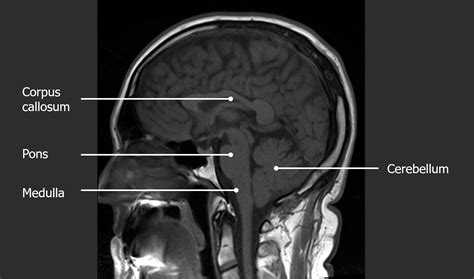

Medical imaging techniques such as Magnetic Resonance Imaging (MRI) and Computed Tomography (CT) scans often use coronal cuts to provide detailed views of the brain. These images are essential for diagnosing and monitoring various neurological conditions. For example, a coronal MRI scan can reveal the extent of a brain tumor or the location of a stroke.

In clinical practice, coronal cuts are used to plan surgical procedures and monitor treatment progress. For instance, neurosurgeons use coronal MRI scans to plan the removal of brain tumors or the implantation of deep brain stimulation electrodes. These images help surgeons navigate the brain’s complex anatomy and minimize damage to healthy tissue.